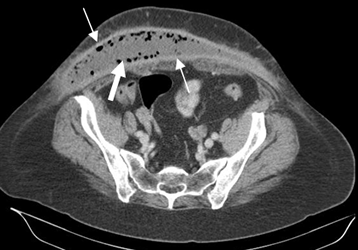

Fig 21. Absceso.

TAC axial. Colección encapsulada de tejidos blandos, que corresponde a absceso. Sus bordes captan el contraste (Flechas delgadas) y existen burbujas de aire en su interior. (Flecha gruesa).